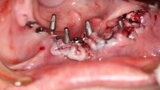

Implantacja z wykorzystaniem szablonu nawigacyjnego 3D